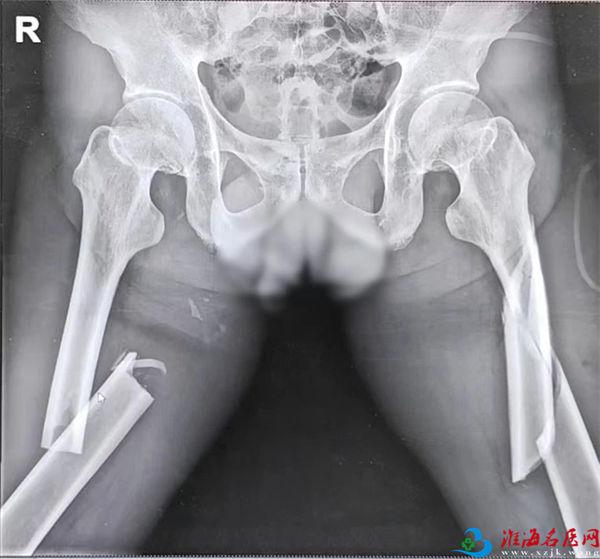

X线检查显示:双侧股骨干粉碎性骨折。

看到胶片上碎裂的股骨影像,孙先生的心沉入谷底,骨头碎成这样,自己还能站起来吗?